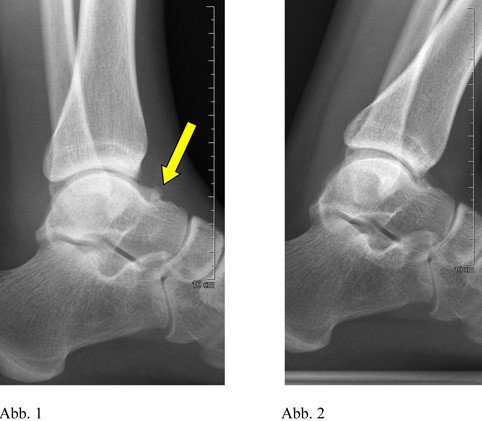

Bei der klinischen Untersuchung fällt eine normale seitengleiche Beweglichkeit im rechten oberen Sprunggelenk auf. Dabei ist eine Druckdolenz im vorderen oberen Sprunggelenksspalt auslösbar. Eine Funktionsaufnahme des Sprunggelenkes in maximaler Streckung zeigt einen knöchernen Konflikt zwischen Sprung- und Schienbein im vorderen Anteil des oberen Sprunggelenkes auf. Dieser Konflikt wird durch einen wahrscheinlich angeborenen Knochensporn verursacht (Pfeil, Abb. 1 und 2).

Röntgenbild Knochensporn